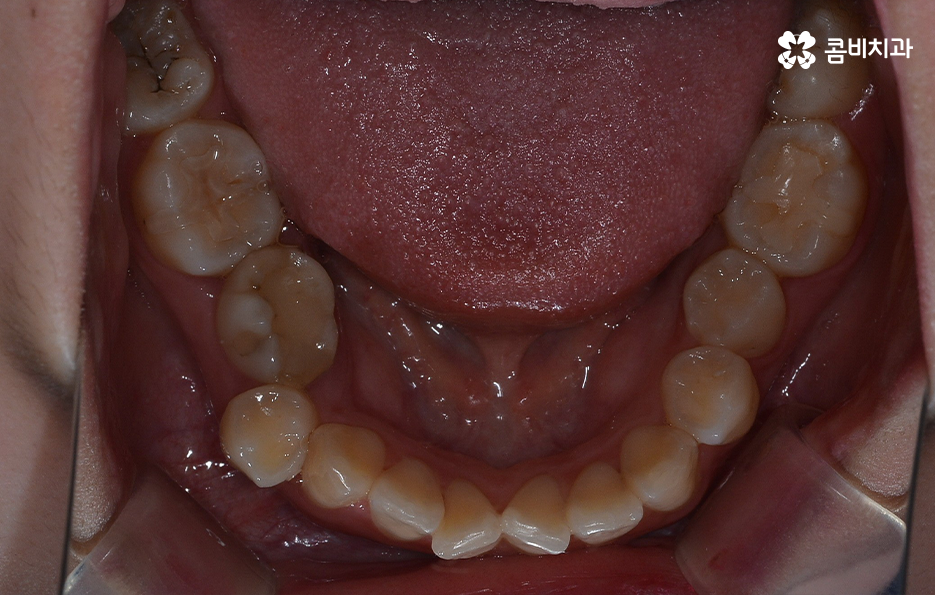

덧니라고 함은 치아의 정상적인 배열에서 많이 벗어난 치아를 의미하고 있는데요. 덧니가 발생하는 원인은 유전적인 원인부터 안좋은 습관 등 다양하겠지만 일반적으로 영구치가 나올 무렵에 치아가 정상적으로 나올 공간이 부족한 상태에서 치아가 맹출되다 보니 덧니가 발생하는 경우가 대표적이라 할 수 있어요

덧니는 윗니와 아랫니에 모두 있거나 앞니에 살짝 있는 수준의 덧니도 있으며 덧니가 심한 경우에는 개방교합으로 인해 입이 잘 다물어지지 않는 경우도 있기 때문에 덧니가 심한 정도에 따라서 치아교정의 계획은 세부적으로 달라질 수 있어요